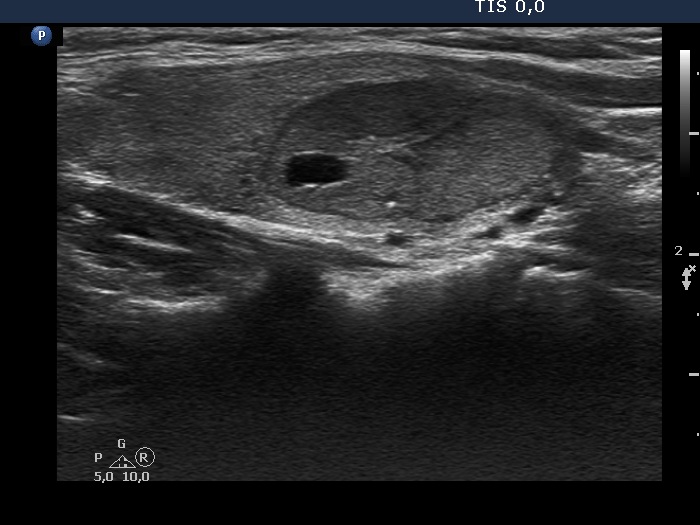

Benign hyperplastic nodule (histological diagnosis) - case 2 |

Hashimoto's thyroiditis without any nodule (histological diagnosis) - case 1520 |

The bright granules lack the dorsal narrowing tail and there are no coexisting similarly bright lines, therefore these granules correspond to punctate echogenic foci.

The coexistence of tiny punctate granules and similarly bright lines is the hallmark of connective tissue. There is a brighter and relatively large granule in the ventral small lesion in the upper image which might be either a punctate echogenic focus or a sign of fibrotic changes.